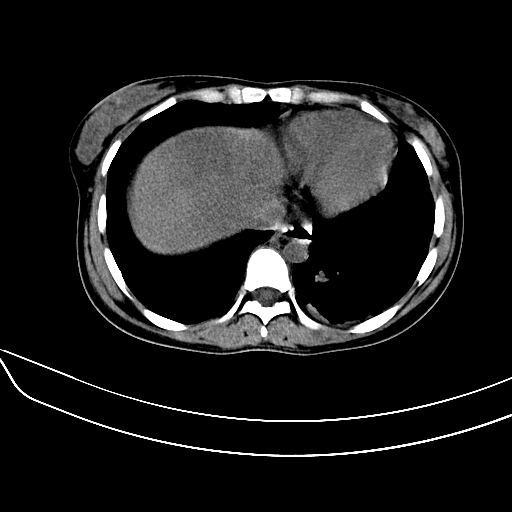

标题: CT7307:糖尿病引起的肝、脾损害?

女,22岁,临床以糖尿病等病史入院,两年前有妊娠合并胰腺炎史,现有多饮、多尿、咳嗽、咳痰、左腰痛、发热等。因多种原因没做增强。

肝、脾增大,内见多发低密度影,少量腹水,左侧肾周筋膜增厚,结合病人糖尿病史,有左腰痛、发热,考虑:糖尿病激发肝脾病变(梗塞?),左侧肾周感染,建议进一步检查。

真可惜,这么年轻就重病缠身,患者肝内,脾,肾,左下肺,左腰大肌均见病变,结合病史考虑感染可能性大。